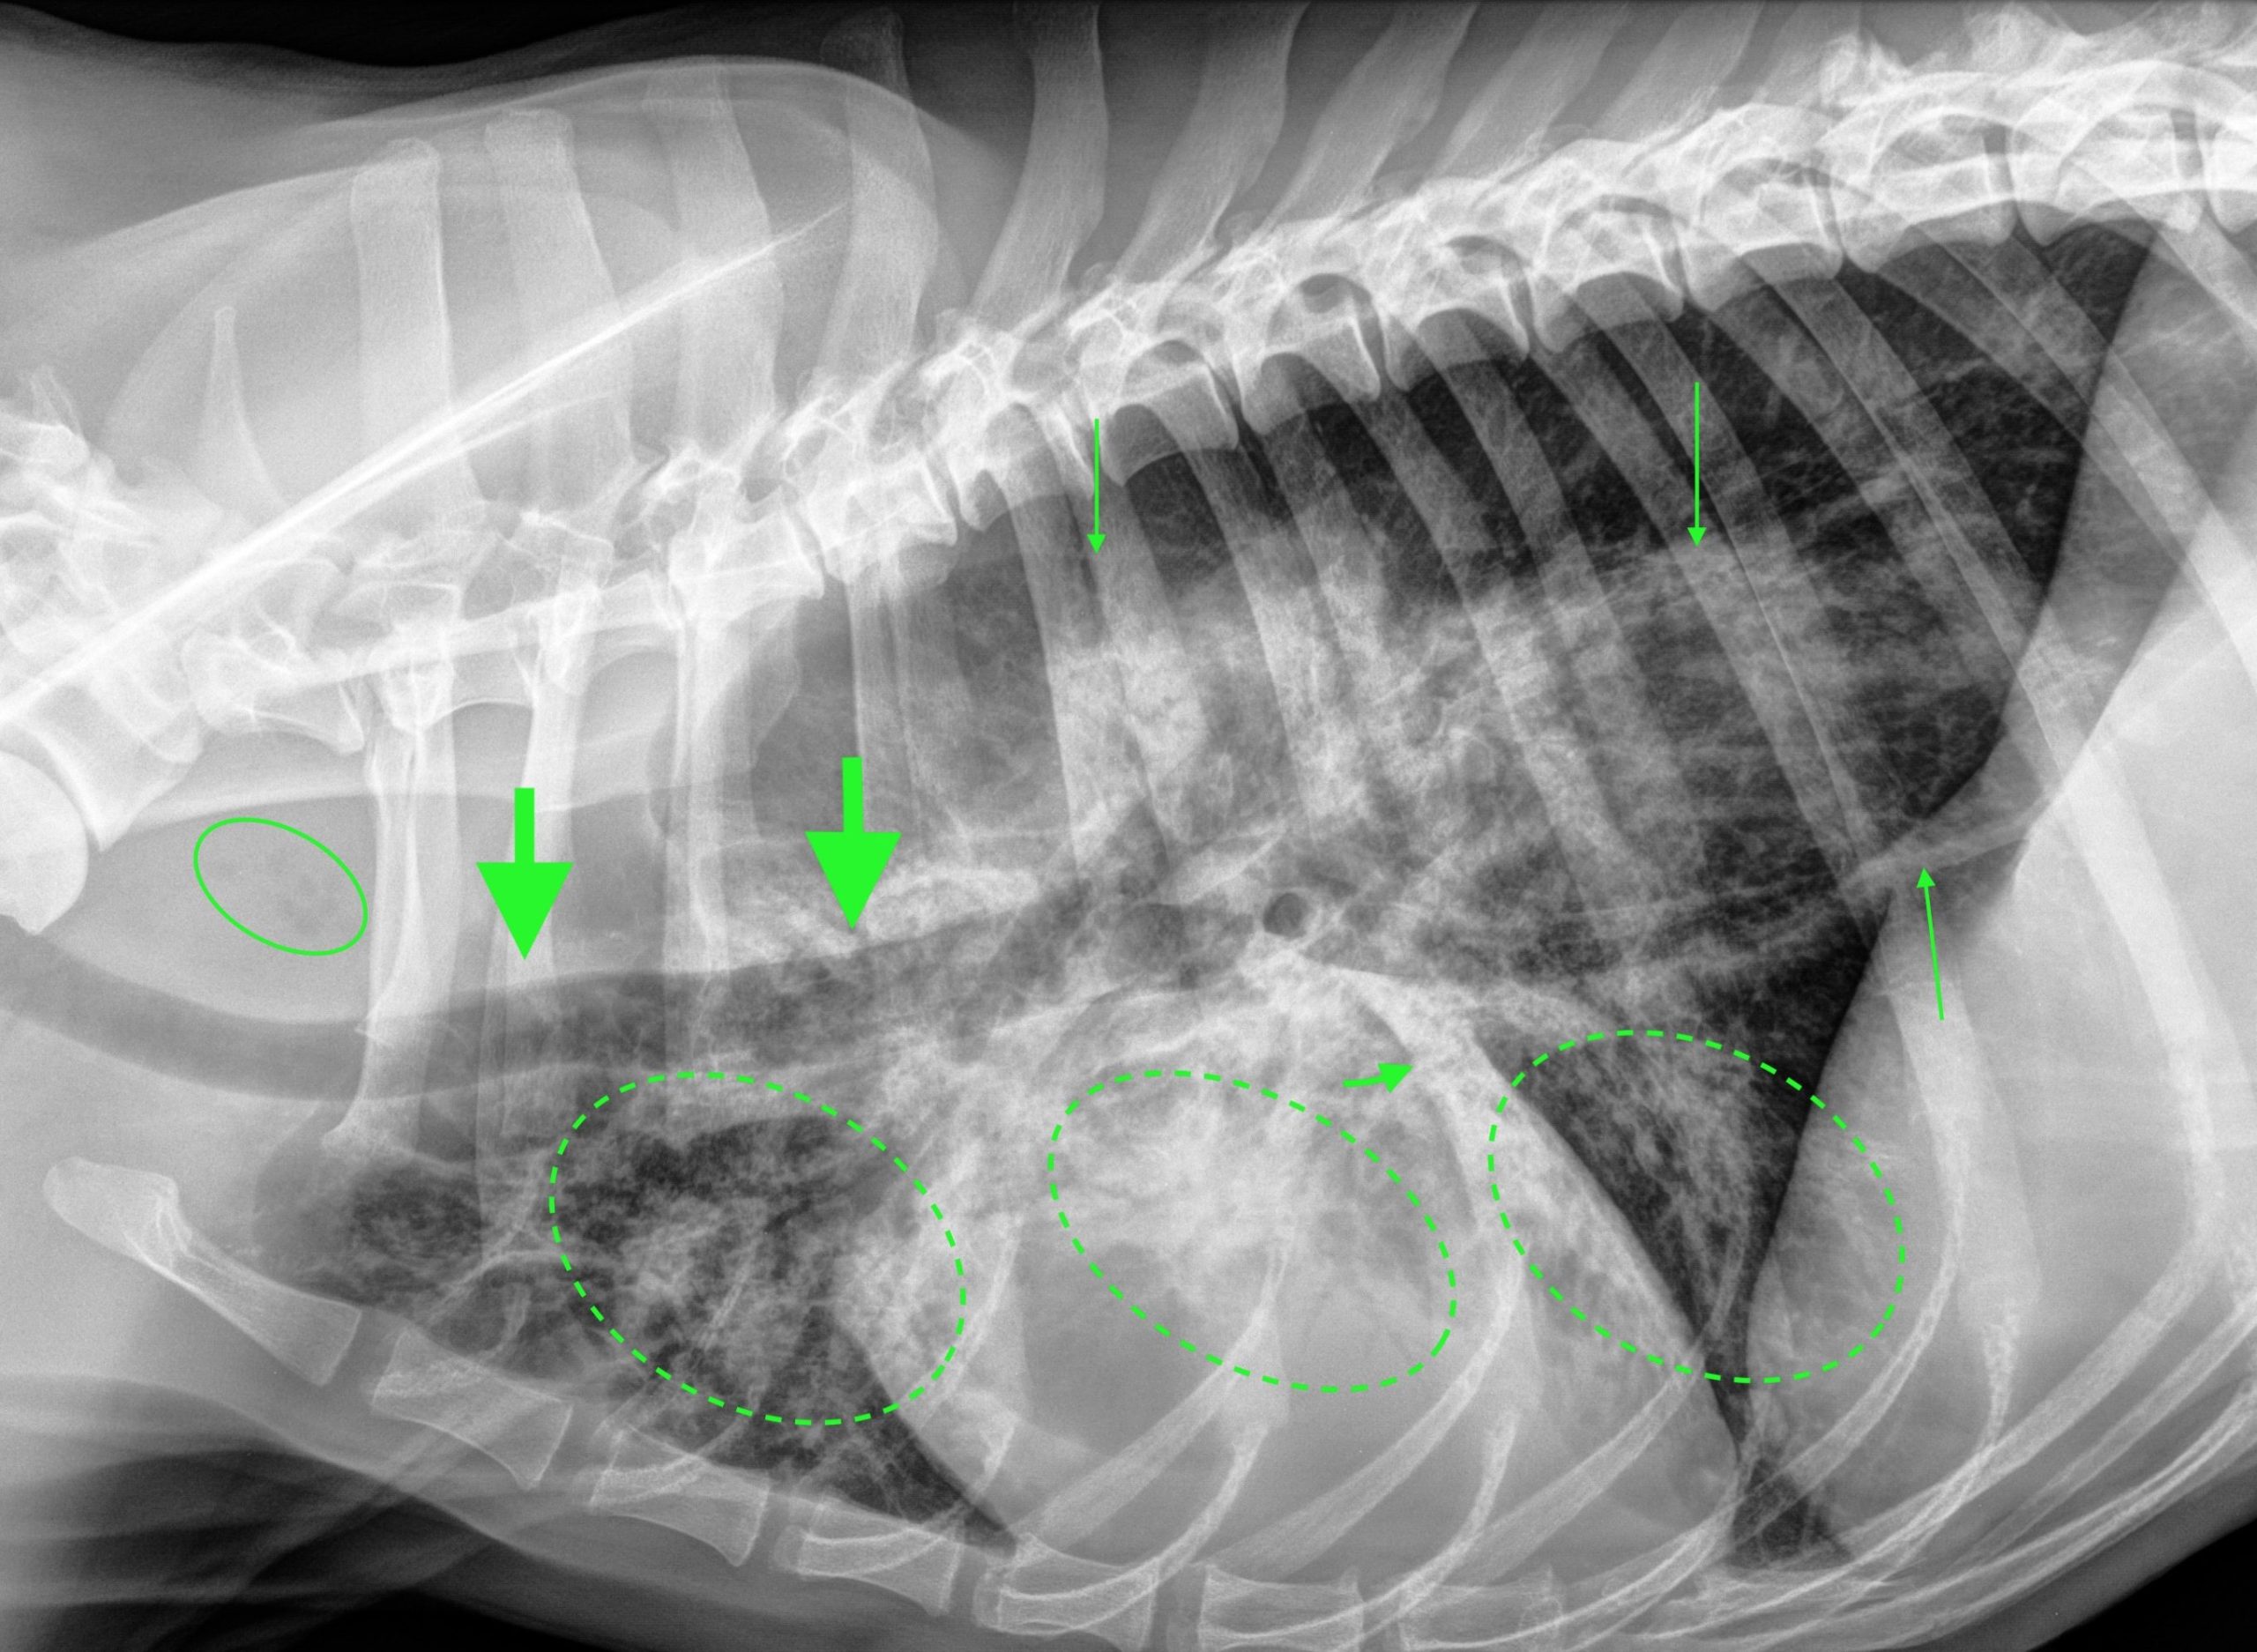

Des radiographies thoraciques sont réalisées (photos 1a & 1b).

On note un effacement de bord gauche de la silhouette cardiaque sur la projection ventrodorsale, une opacification augmentée dans les lobes pulmonaires craniaux droit et gauche, moyen droit et caudal gauche, une perte de visualisation des vaisseaux pulmonaires et des bronchogrammes aériques et un signe lobaire du lobe caudal gauche (sur la projection latérale). Ces lésions sont compatibles avec une consolidation pulmonaire lobaire multifocale ventrale.

Le reste du parenchyme pulmonaire présente également une opacification bronchique avec des images en anneaux et en rails, sévère cranialement et discrète caudalement.

Enfin, on note une dilatation gazeuse marquée de l’œsophage thoracique, se manifestant par :

La consolidation pulmonaire ventrale bilatérale lobaire et l’opacification bronchique sont compatible prioritairement avec une bronchopneumonie par fausse déglutition, secondaire à la dilatation œsophagienne sévère. Cette dilatation généralisée peut avoir une origine fonctionnelle (mégaoesophage idiopathique ou congénital, troubles neuromusculaires, œsophagite) ou moins probablement mécanique (obstruction œsophagienne distale) (1).